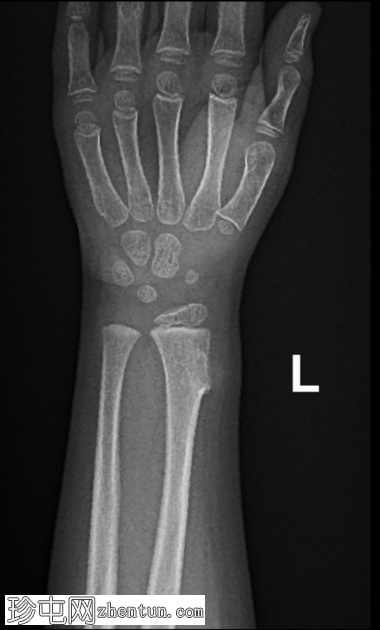

正位片

可见桡骨远端干骺端前外侧有一骨性增生。病变与母骨皮质和髓质相连。边界清晰。无皮质破损、骨膜反应及相关软组织肿块。邻近尺骨外观正常。无骨折或脱位。